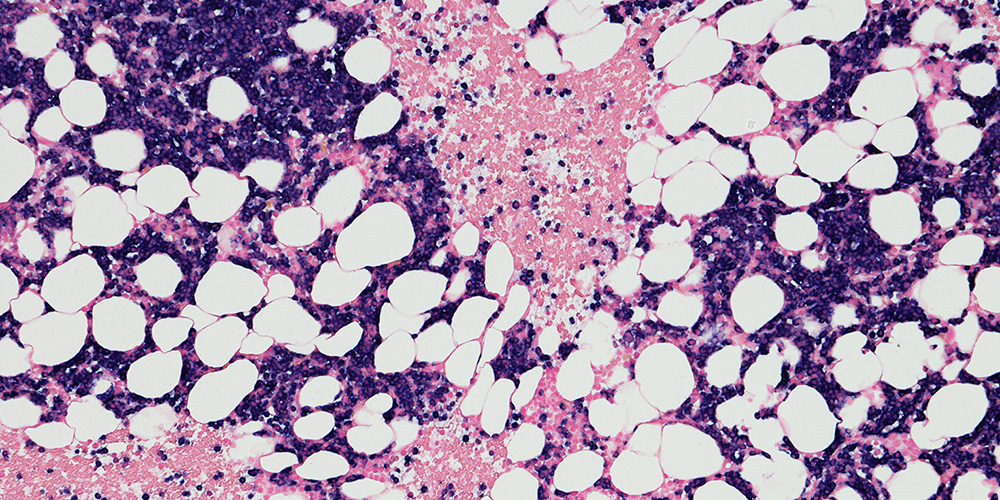

The Seth Corey lab studies bone marrow failure, myelodysplastic syndromes and myeloid malignancies.